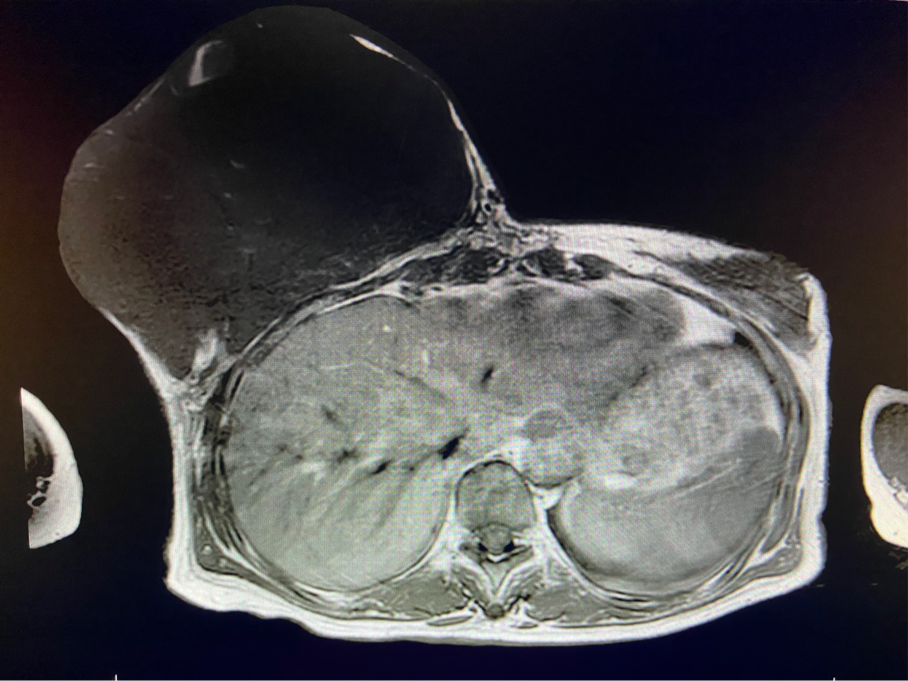

6個(gè)月前,王女士能感覺到右乳腫物明顯增大至“鴨蛋”一般,而且伴有局部皮膚瘙癢及輕度脹痛,可這次王女士并沒有那么幸運(yùn),服藥3個(gè)月不僅沒有控制住腫物,脹痛也越發(fā)嚴(yán)重,超聲檢查提示:右乳囊實(shí)性占位,最大前后徑約10.8cm,右腋窩多發(fā)腫大淋巴結(jié),遂行右乳腫物穿刺活檢術(shù),術(shù)后病理檢查提示:右乳腫物穿刺乳腺組織2條,均可見導(dǎo)管囊性擴(kuò)張,部分區(qū)域間質(zhì)纖維增生,其中1條內(nèi)導(dǎo)管上皮成普通型增生。輾轉(zhuǎn)當(dāng)?shù)囟嗉裔t(yī)院藥物治療后,錢沒有少花,但是療效甚微。

2周前,王女士的右乳外下方皮膚破潰,伴大量滲液,還發(fā)出陣陣惡臭。經(jīng)多方打聽,王女士從外地來到西安國(guó)際醫(yī)學(xué)中心醫(yī)院甲乳外科劉曉敏主任處就診。入院后,迅速完善了一系列相關(guān)術(shù)前檢查:王女士的雙乳外形不對(duì)稱,右乳約22?20cm,皮膚水腫明顯并可見靜脈曲張。右乳外下象限皮膚可見局部破潰,創(chuàng)面有3處,共約6?4cm大小,創(chuàng)面呈暗紅色,伴有血性滲出及惡臭,局部皮膚溫度升高。右側(cè)腋窩可觸及腫大淋巴結(jié)。

該患者右乳巨大腫物術(shù)前初步考慮乳腺葉狀腫瘤可能,因腫瘤太大,幾乎遍及整個(gè)右側(cè)乳房,為保證“無瘤原則”,術(shù)中切除范圍位置未知,極有可能出現(xiàn)皮瓣缺損。于是,經(jīng)過和整形醫(yī)院郭樹忠院長(zhǎng)、整形外科王愛武主任的討論,提供了兩種手術(shù)方式,一是創(chuàng)面修復(fù)(植皮或轉(zhuǎn)移皮瓣修復(fù)創(chuàng)面),二是乳房再造,與患者及家屬溝通后,決定先解決腫物,3年病情不再復(fù)發(fā)后,可以再考慮乳房重建。